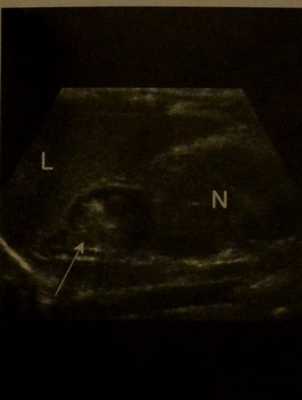

Кровоизлияние в надпочечники у новорожденного с перинатальной асфиксией. УЗИ. Острое кровоизлияние в правый надпочечник (стрелка). Кровоизлияние проявляется гиперэхогенной неоднородной эхоструктурой. L- печень, N - правая почка.

Что покажет УЗИ надпочечника при кровоизлиянии у ребенка

- Гомогенное, гиперэхогенное образование в надпочечниках, позднее становится неоднородным и гипоэхогенным

- Потеря типичной кортико- медуллярной дифференцировки

- В поздней стадии может определяться полностью кистозное поражение

- Смещение почек в каудальном направлении